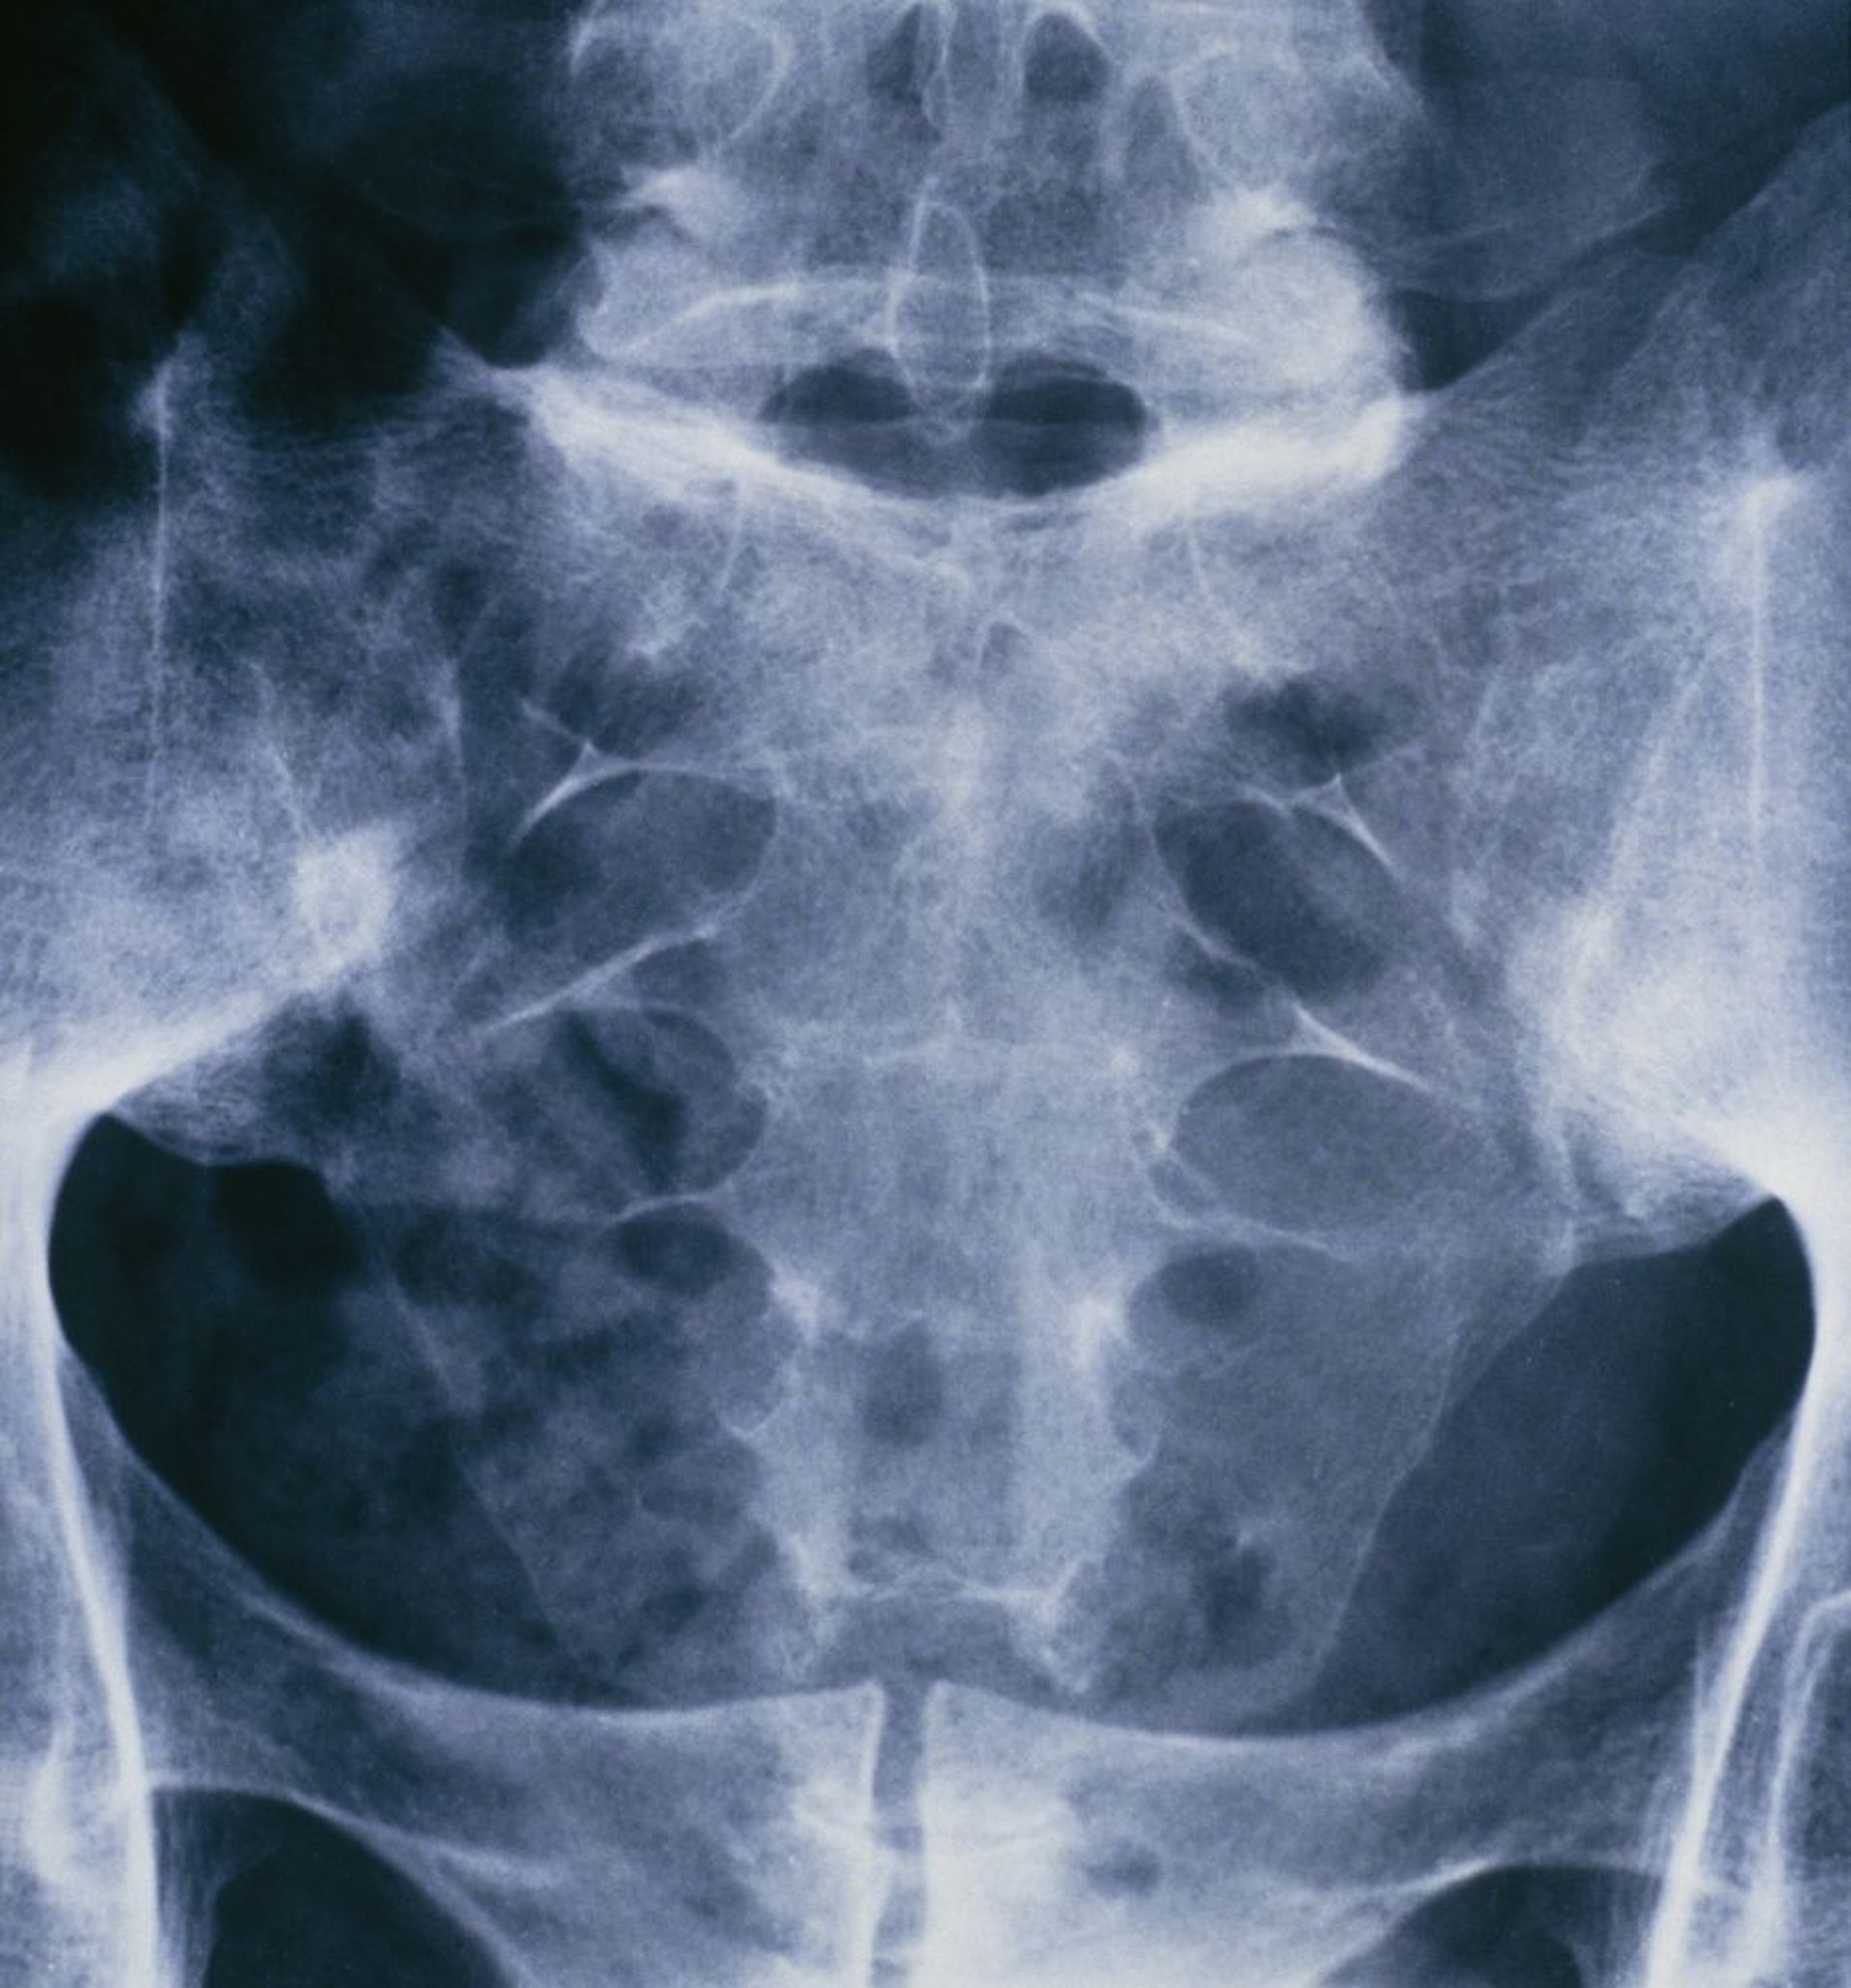

Анкилозирующий спондилит (сакроилеит)

Этот рентгеновский снимок таза и крестцового отдела позвоночника человека, страдающего анкилозирующим спондилитом, демонстрирует слияние обоих крестцово-подвздошных суставов.

ST. BARTHOLOMEW'S HOSPITAL, LONDON/SCIENCE PHOTO LIBRARY